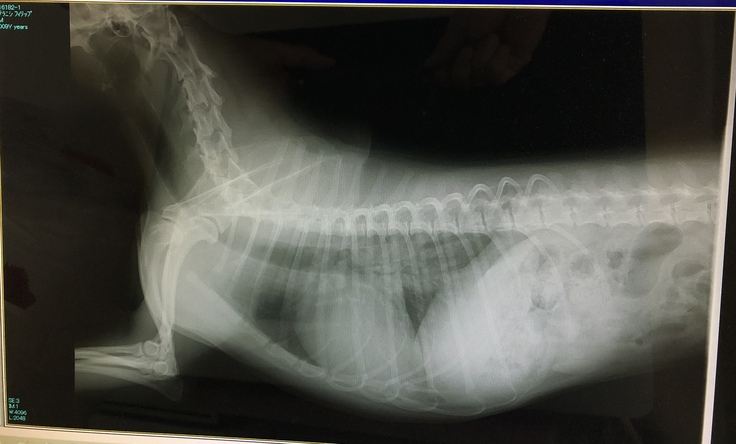

【肥大した心臓のレントゲン】

僧帽弁閉鎖不全症とは、心臓の左心房と左心室の間に位置する僧帽弁(血液を送り出すために開いたり閉じたりする機能を持つ弁)が、なんらかの原因で変性し、閉鎖不全が生じるために起こります。僧帽弁の閉鎖不全が起こると、左心室から左心房へ血液が逆流し血液の循環不全がおこるためさまざまな症状が引き起こされます。

重症になると、肺水腫(肺に液体がたまり、酸素と二酸化炭素の交換がスムーズにいかなくなるため、呼吸が苦しくなる病気)や呼吸困難、チアノーゼ(舌の色が紫色になる)などの症状を起こし、死に至る場合もあります。

原因は僧帽弁閉鎖不全による急性肺水腫で、救急に来なければ命に関わっていたと医師に言われました。